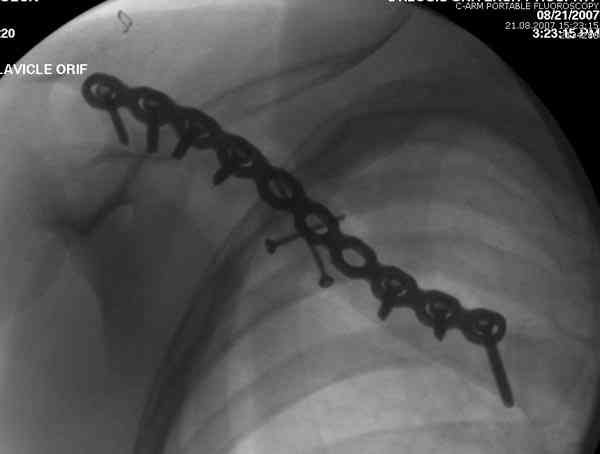

При оперативном лечении ключицы необходимо применить методику Inderect Reduction Technique с обнажением кости только с той стороны, где устанавливается пластина.

При применении спиц из-за неудобного вектора один из фрагментов необходимо приподнять от грудной клетки и, тем самым, приподнимая ухудшают, заднее кровеснабжение.

Спицы противопоказаны не только из-за отсутствия стабильности, также из-за их опасной миграции. Описаны много случаев миграции спиц даже в каротидную артерию.